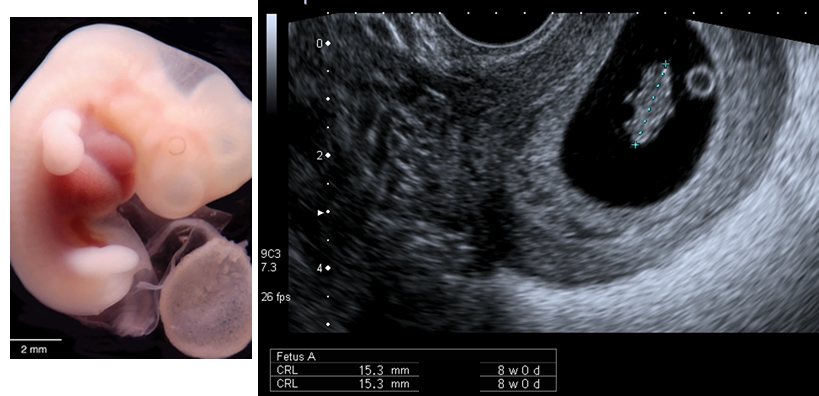

The embryo has grown by 5 mm, measuring the crown-rump length.

| Fig 1a Reproduced with kind permission from Brad Smith, University of Michigan; NICHHD: NO1 HD 6 3257 |